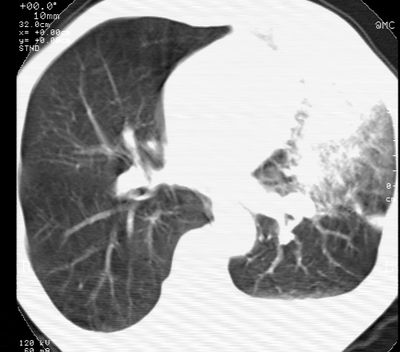

左肺门肿块,相应支气管闭塞,左肺上叶、舌叶大片及散在高密度影,部分呈不张改变,两肺纹粗乱,左侧胸腔积液。考虑左侧中央型肺癌伴阻塞性改变。

左肺门见巨大软组织肿块影,直径约--,境界清,左上肺叶支气管变窄,左上肺舌叶见大片状密实影,余肺纹理增多、紊乱、纤细、部分网格状,两肺透亮度增高,纵隔内见增大多发淋巴结影,心影略左偏,左侧少量胸腔积液。

左侧中央型肺癌伴左上肺舌叶不张、纵隔淋巴结转移,左侧少量胸腔积液。